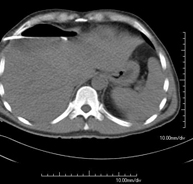

- Abdomen CT

Diagnostic test that involves obtaining high-definition anatomical images of the abdomen (liver, gallbladder, bile duct, pancreas, spleen, stomach, intestines, kidneys, vascular structures, bladder, uterus and ovaries, etc.) using CT (computed tomography) equipment. These images are then studied at a workstation capable of producing two-dimensional reconstructions in different spatial planes, and also 3D (volumetric) reconstructions. Most studies require the use of iodinated contrast to improve image definition.

- Abdominal and pelvic CT

Diagnostic test that consists of obtaining high-definition anatomical images (bone structures, vascular structures, liver, pancreas, gallbladder, kidneys, adrenal glands, spleen, small and large intestine, bladder, uterus and ovaries, prostate and seminal vesicles, ureters, etc.) using CT (computed tomography) equipment. Most studies require the use of iodinated contrast.